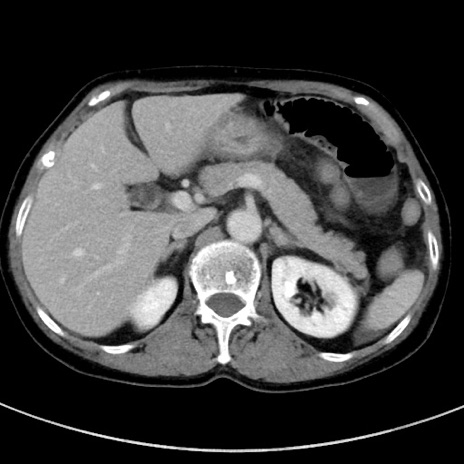

冠状断像

【症例】70歳代女性

【主訴】下腹部痛・嘔吐

【現病歴】2日前より腹痛あり。昨日嘔吐あり。症状改善しないため来院。

【既往歴】胃GISTに対して胃部分切除後。

【身体所見】BT 37.1℃、BP 128/77mmHg、腹部:平坦・軟、下腹部に圧痛あり。

【データ】WBC 10200、CRP 0.31